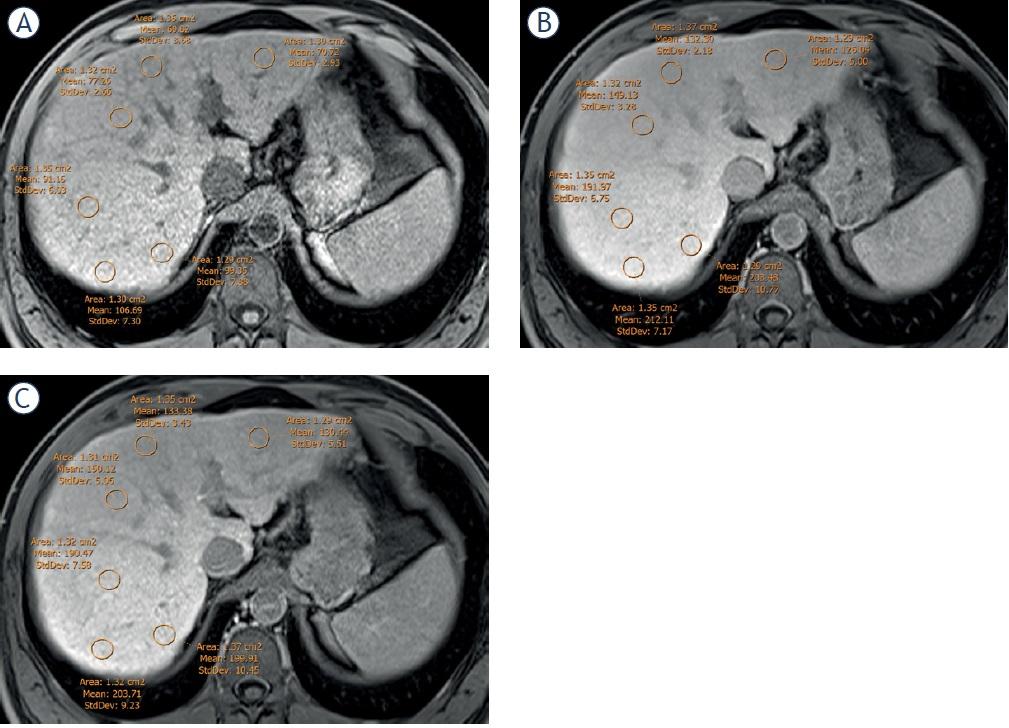

Different MR-derived parameters focused to estimate the amount of Gd-EOB-DTPA liver uptake were calculated in the 10 and 20 minutes HBP. In all these indices, greater values mean more liver uptake of Gd-EOB-DTPA in the HBP. The quantitative assessments were done by C.C. (Figure 2). All formulas are summarized in Table 1 and described in detail in supplemental material.

Location of the 6 regions of interest (ROIs) in the liver parenchyma, to calculate the liver signal intensity (LSI) in the pre-contrast sequence (LSIpre) (A), at 10 minutes (LSI10) (B) and at 20 minutes (LSI20) hepatobiliary phase (C). Four of the ROIs were located in the anterior and posterior segments respectively of the right hepatic lobe, and two more were placed in the lateral and medial segments of the left lobe respectively. ROIs were drawn avoiding the inclusion of vascular structures and possible focal liver lesions.

Relative Liver Enhancement (RLE): RLE10 and RLE20 establish the relationship between the SI of the liver parenchyma in the 10 minutes (LSI10) and the 20 minutes HBP (LSI20), and the liver SI before contrast injection (LSIpre).25

Liver to Spleen/muscle/Kidney Contrast Ratios: These indices determine the relationship between the SI of the liver and the SI of the spleen (LSCR), muscle (LMCR) and kidney (LKCR). To estimate the LSCR, an additional ROI was drawn on the spleen, over the same three images selected previously.26 (Figure 3A) For LMCR, an additional ROI with an average area of 100 mm2 was drawn on the right paraspinal muscle. (Figure 3B). Finally, for LKCR an additional ROI with an average area of 0,5 to 1 cm2 was drawn on the upper pole of the right kidney (Figure 3C).